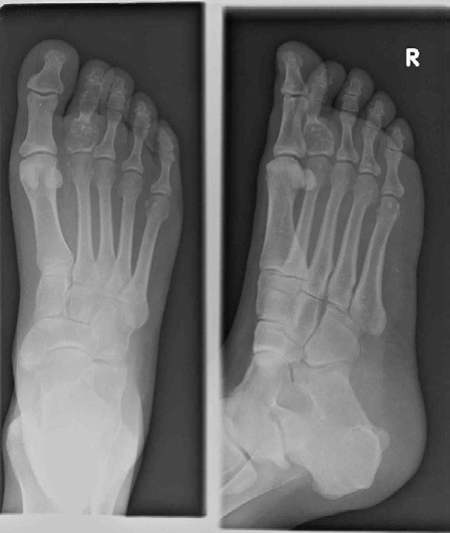

Orthopaedic oncology Structured oral examination question 2: Enchondroma Figure 7.2 Enchondroma. EXAMINER : T…